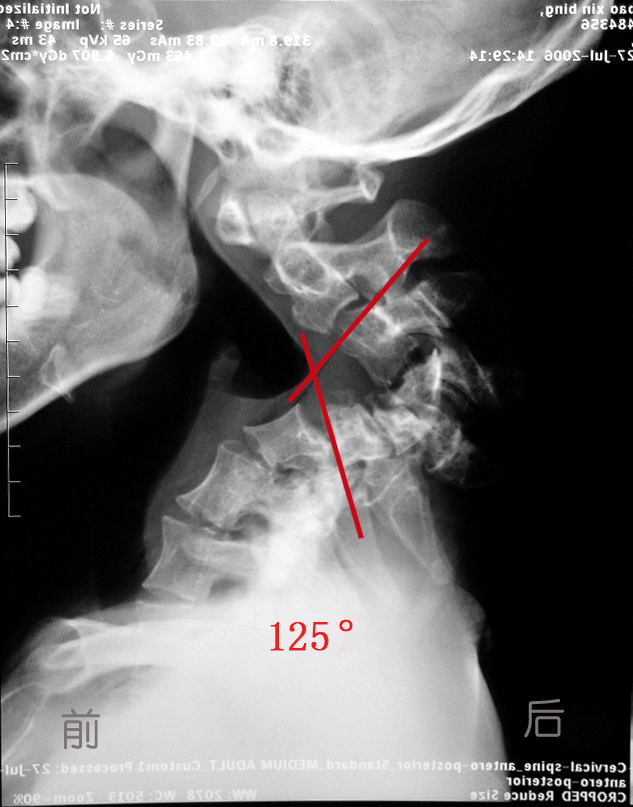

-------125 °颈椎重度后凸畸形奇迹般矫正

对于眼前这个达到125°严重颈椎后凸畸形的病人,北医三院经验丰富的骨科医生们也感到非常惊讶。这是一个年仅18岁的男孩,名叫包新(化名)。据了解, 患者在上小学时就开始感觉脖子疼痛,到医院拍片检查时发现颈椎有轻度的后凸畸形,但外观并没有太大的异样,并没有引起家长的充分重视。以后发现其后颈部渐渐地鼓了起来,直到今年,病情突然变得严重,不仅颈椎从外观看后凸明显,还出现了手脚麻木、活动不灵活,走路像踩在棉花上一样,摇晃不稳等症状。患者在当地走访了多家医院,并采取牵引的方法治疗,但效果并不满意。他的头已经抬不起来,几乎不能仰头看天;因为前次颈椎牵引后出现的并发症,左胳膊已经抬不起来了,走路也是摇摇晃晃的,没有人扶着,几乎就不能自己站立和行走… …

综合国内外文献资料,目前还没有发现颈椎后凸畸形如此严重的病例,且文献资料中所介绍的一次手术矫正畸形的方法大多手术难度大,矫形效果差,手术中脊髓损伤的风险极高。即使在手术前的轴向牵引过程中,导致脊髓损伤的风险也比较高。患者以前在别的医院所进行的颈椎轴向牵引,虽牵引重量很小,也还是不幸地导致了脊髓损伤,此后更要慎重。

最后,治疗小组决定采用循序渐进的策略,采用松解、牵引复位、最后矫形固定的方法。于七月三十一日首先做了一个颈椎前后路联合的充分松解手术;再创新性地采用了一种全新的“平衡悬吊式牵引”方法,在牵引过程中,将项背部悬空,依靠头颅的自身重量,使颈椎后凸的角度逐渐缩小,通过将近4个星期的“平衡悬吊式牵引”,最后拍片发现病人原本125度的颈椎后凸角度已经减少到了25度左右,而且牵引过程中没有出现脊髓损害加重的常见并发症。一个半月后,治疗小组又对其进行了一次颈椎前后路的联合手术,这一次,就用钛板螺钉内固定的手术方法从前后方向将颈椎固定在了最后牵引到达的后凸25度。

术前X线 术后X线